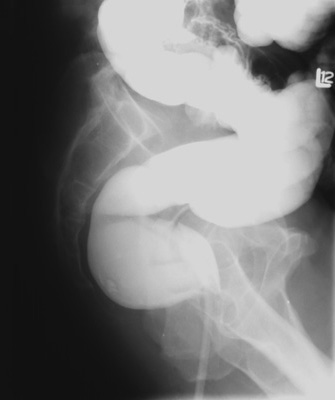

Left lateral rectum - vertical central

ray, 14" x 14" cassette